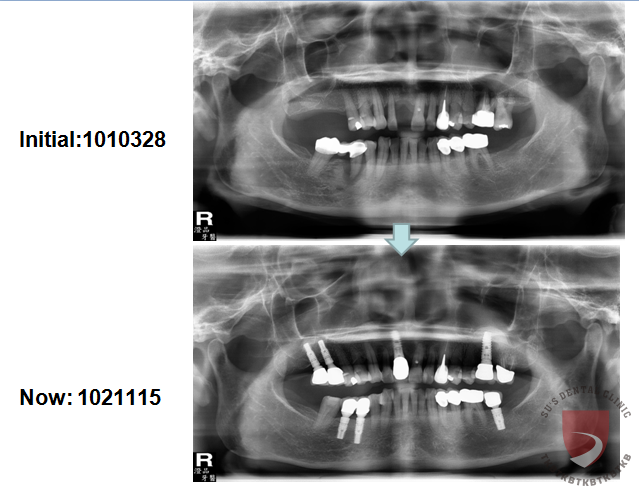

高蛀牙率合併牙周病 牙齒移位

牙周病造成多處缺牙